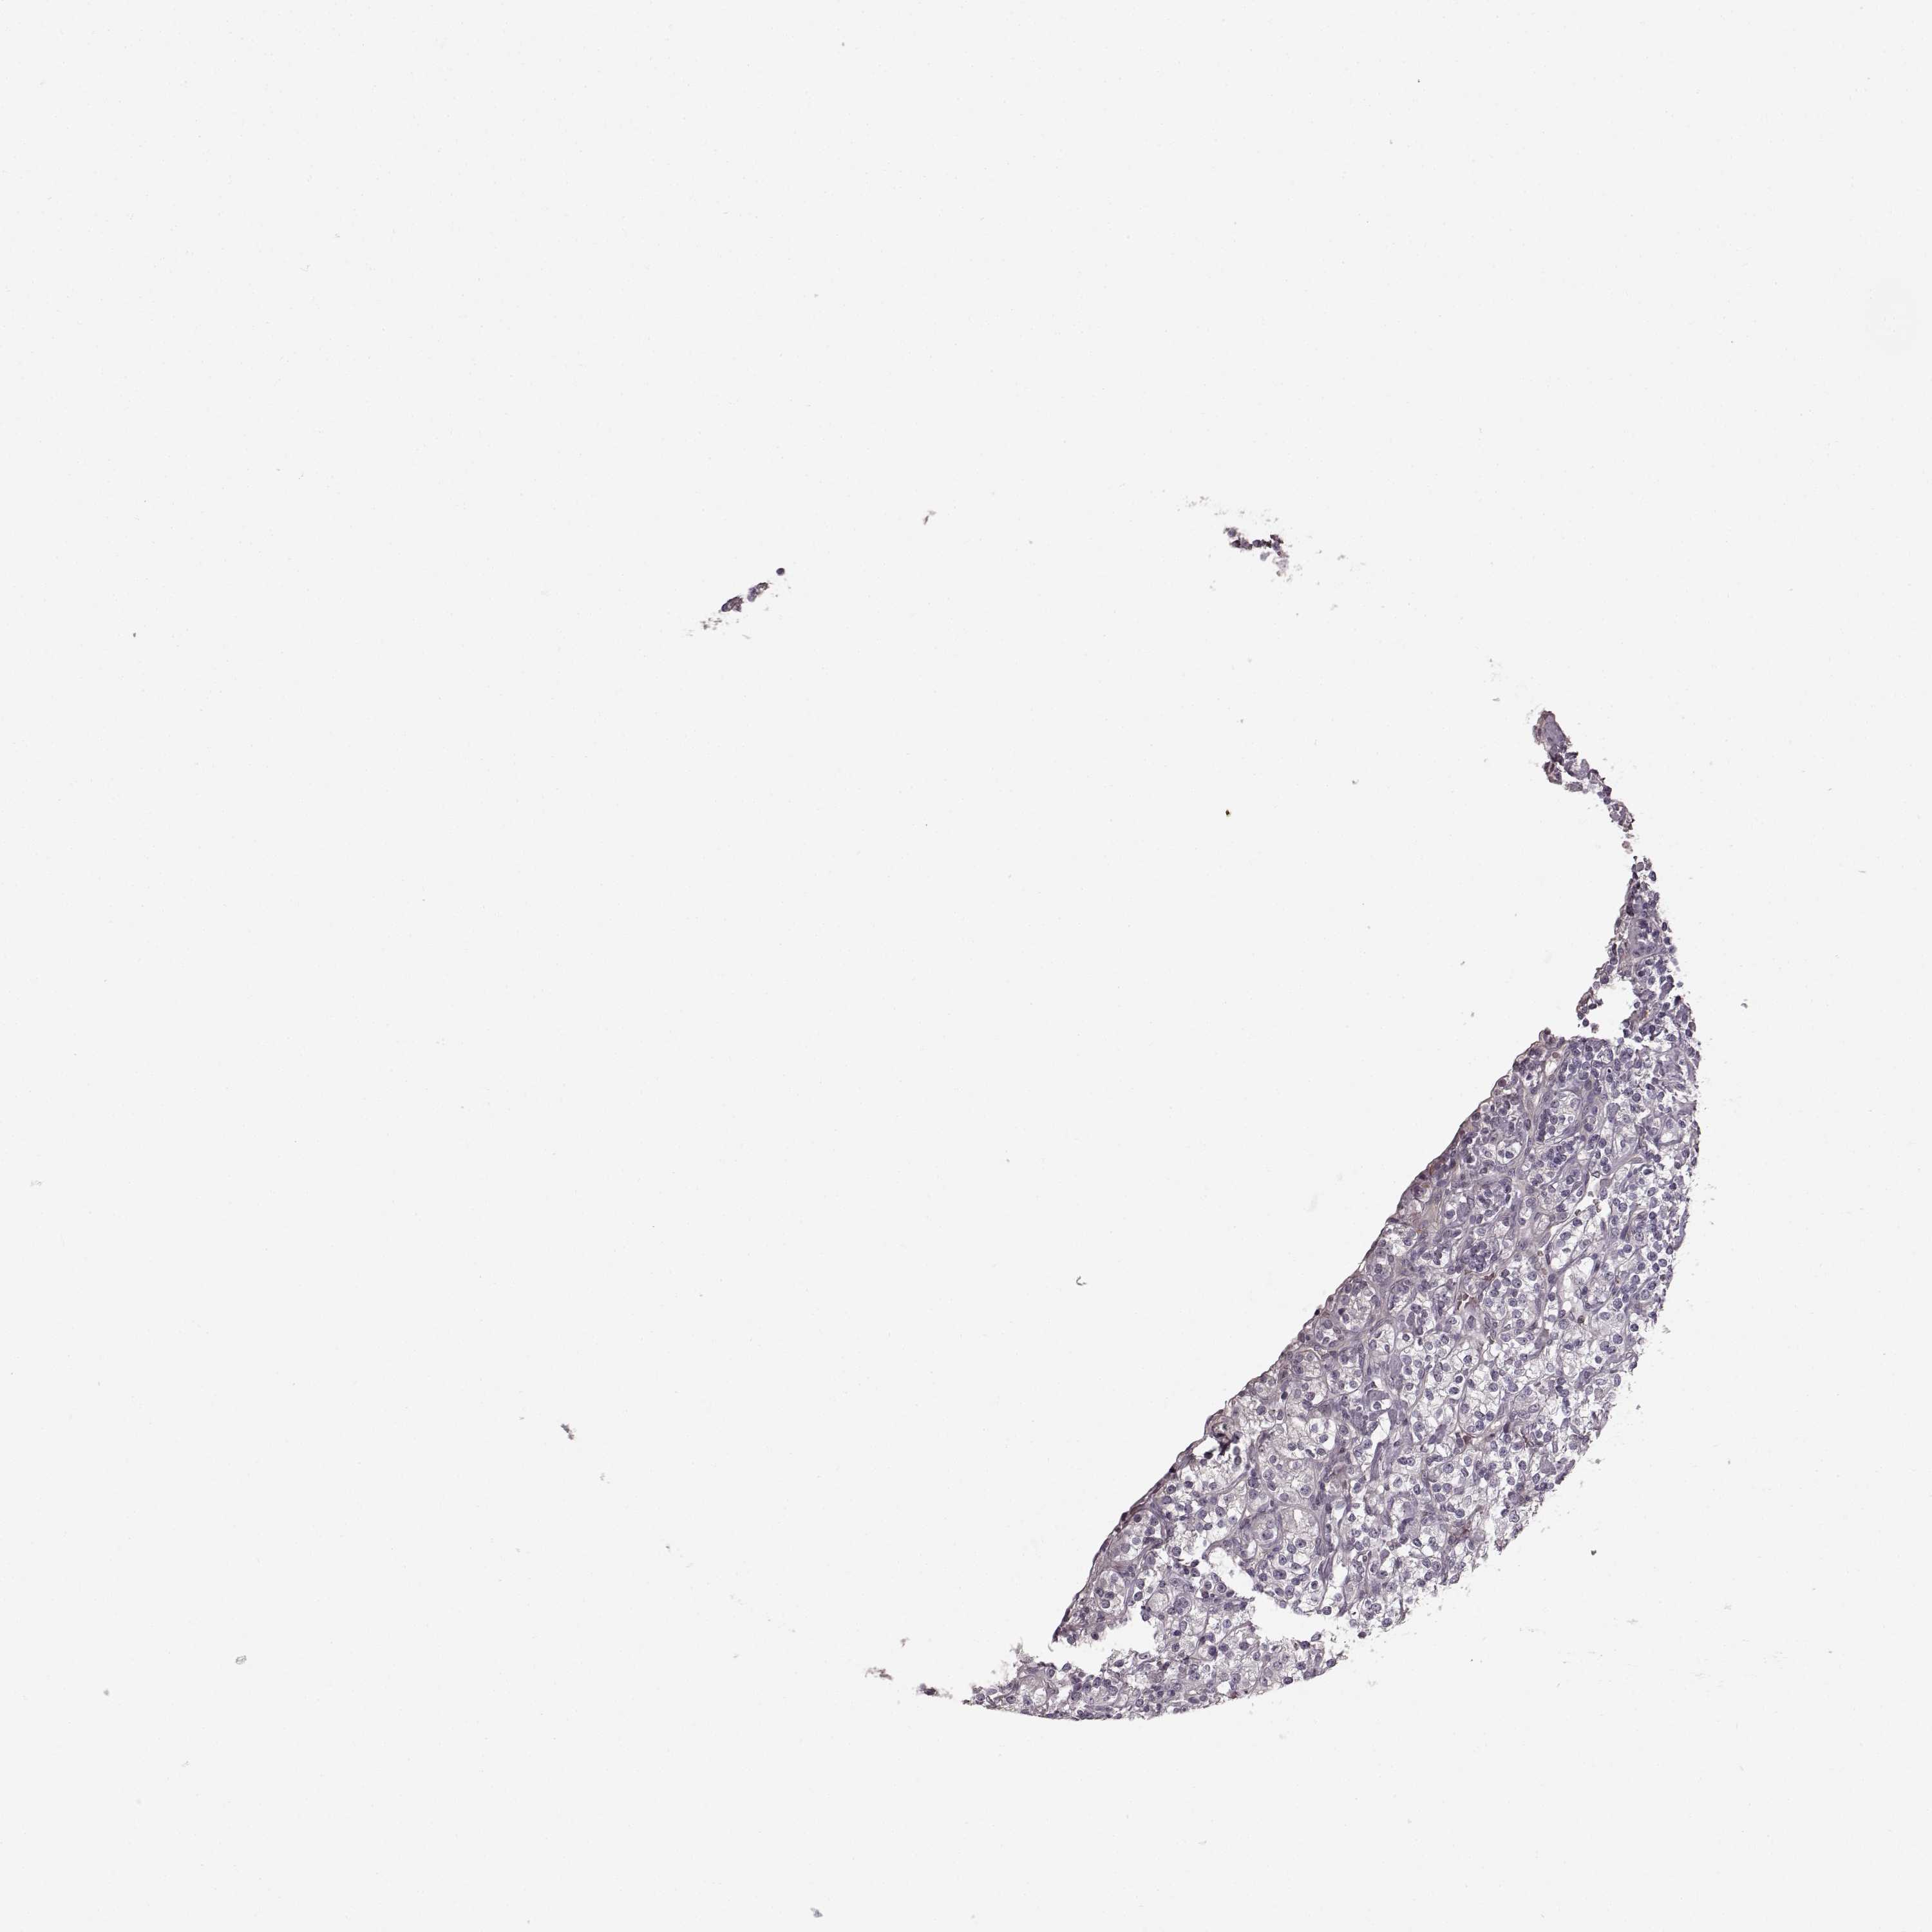

KIDNEY RENAL CLEAR CELL CARCINOMA (VALIDATION) - Interactive survival scatter ploti

The Survival Scatter plot shows the clinical status (i.e. dead or alive) for all individuals in the patient cohort, based on the same data that underlies the corresponding Kaplan-Meier plots. Patients that are alive at last time for follow-up are shown in blue and patients who have died during the study are shown in red.

The x-axis shows the expression levels (FPKM) of the investigated gene in the tumor tissue at the time of diagnosis. The y-axis shows the follow-up time after diagnosis (years). Both axes are complimented with kernel density curves demonstrating the data density over the axes. The top density plot shows the expression levels (FPKM) distribution among dead (red) and alive patients (blue). The right density plot shows the data density of the survived years of dead patients with high and low expression levels respectively, stratified using the cutoff indicated by the vertical dashed line through the Survival Scatter plot. This cutoff is automatically defined based on the FPKM cutoff that minimizes the p-score. The cutoff can be changed by dragging the vertical line or by entering a cutoff value in the square labeled "Current cut-off".

Under the Survival Scatter plot the p-score landscape (black curve; left axis) is shown together with dead median separation (red curve; right axis). Dead median separation is the difference in median mRNA expression between patients who have died with high and low expression, respectively. It is calculated as follows: median FPKM expression of dead patients with high expression - median FPKM expression of dead patients with low expression. This is intended to aid the user in visually exploring custom cutoffs and the associated p-scores and dead median separation.

Individual patient data is displayed and can be filtered by clicking on one or more of the category buttons on the top of the page. Categories describing expression level and patient information include: high, low, alive, dead, female, male and tumor stages. The scale of the x-axis can be toggled between linear and log-scale by clicking on the "x log" button. Mouse-over function shows TCGA ID, patient information and mRNA expression (FPKM) for each patient.

& Survival analysisi

Kaplan-Meier plots summarize results from analysis of correlation between mRNA expression level and patient survival. Patients were divided based on level of expression into one of the two groups "low" (under cut off) or "high" (over cut off). X-axis shows time for survival (years) and y-axis shows the probability of survival, where 1.0 corresponds to 100 percent.

PRKCE is not prognostic in Kidney Renal Clear Cell Carcinoma (validation)

Best expression cut offi

: 5.72

Average pTPM 7.1

Number of samples 100